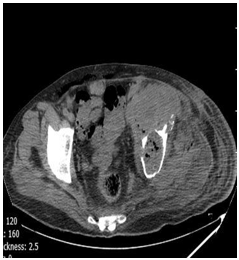

Abdominal ultrasound did not show hepatic or other visceral involvement. Pelvic ultrasound indicated a collection include necrotic tissues, gas bubbles, and discharge in the left side of pelvic cavity. Chest x-ray (CXR) was normal. A computed tomography scan showed destruction lesions in the left hemi pelvis, sacrum, and the left proximal femur, as well (Figures 2-5).

Figure 3: CT-scan of pelvic show distraction of iliac, scum bone, hipe joint and swelling of boutack with air.